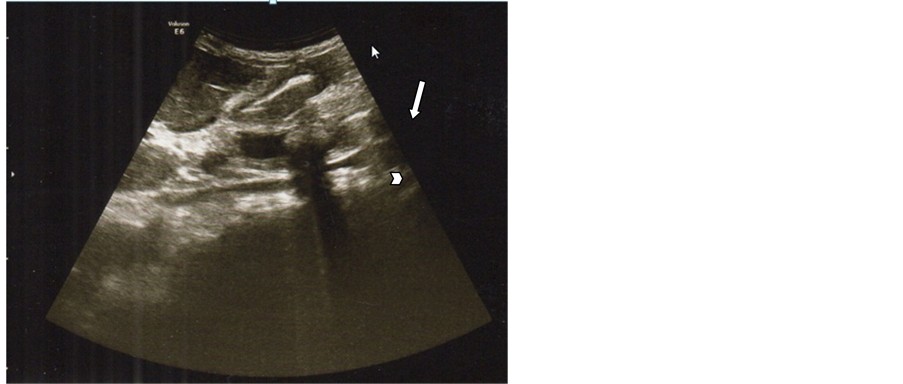

Careful scanning of the entire course and caliber of the duct system whenever possible was done from portahepatis to pancreatic head to trace the extent of the duct dilatation and to localize the level of obstruction. CBD was identified using color Doppler us to differentiate from nearby vessels (portal vein and hepatic artery) (Figure 5). The diagnosis of choledocholithiasis was made when intraluminal echogenic focus with or without acoustic shadowing was demonstrated.

Figure 5. Color Doppler Ultrasound of portahepatis show dilated CBD with no stone by ERCP impacted lower CBDS.